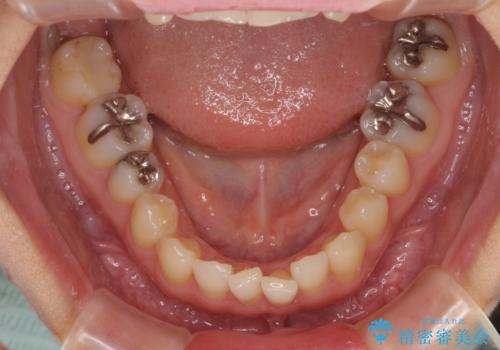

八重歯を改善 ワイヤー装置での抜歯矯正

下顎歯列の叢生は軽度であることと、口元の突出感が全くなかったことから、八重歯解消のために上顎左右第一小臼歯を抜歯し、ワイヤー装置にて矯正治療を行うこととしました。

八重歯をスムーズに解消するために、補助装置を用いることで速やかに歯列を整えることができました。